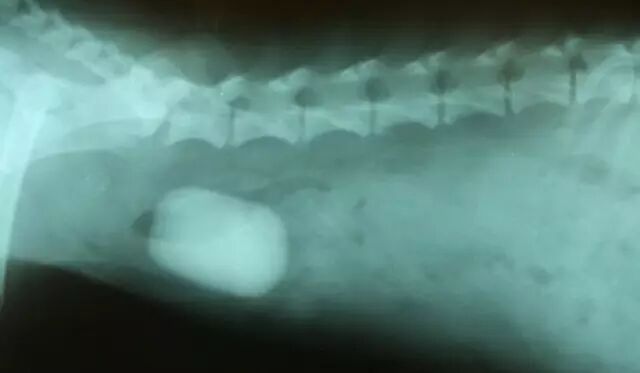

犬、猫胃肠异物:①多发于幼犬及老龄猫;②病因:吞食异物,如被毛、骨骼、针等;③症状:呕吐、胃炎、食欲差或出现贪食,但只吃几口就走开;④诊断:触诊、x线检查;⑤防治:当为光滑异物时,用阿扑吗啡或隆朋催吐;当为尖锐异物,可投服浸泡牛奶的脱脂小棉球或小的肉块;当为毛球时,可投服石蜡油。

犬、猫肠便秘:①多发于老龄犬猫;②病因:饲料中混有骨头;肛门脓肿、肠套叠等;③症状:反复努责而排不出粪便;触诊可摸到大肠内成串的干硬粪块,按压时有疼痛表现,肛门指检过敏;x线检查可见肠管扩张状态,其中含有致密粪块的异物阴影。

④诊断:X线检查,雌犬膀胱探诊,公犬尿道探诊,尿常规,血常规检查;